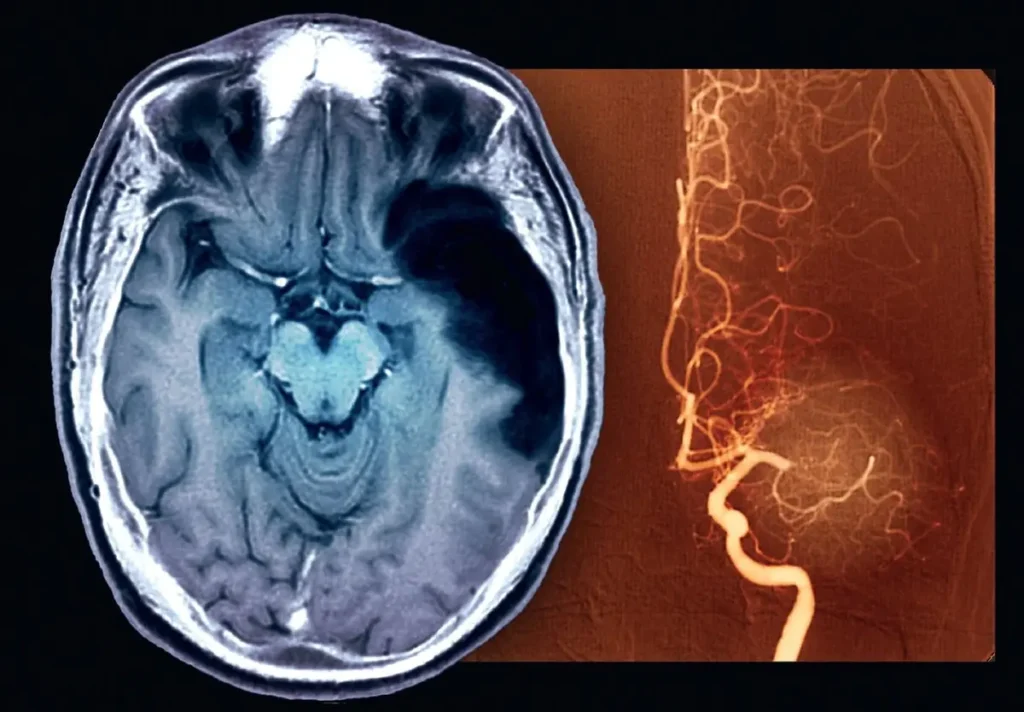

In der Notaufnahme erfolgt zunächst eine neurologische Untersuchung. Bildgebende Verfahren wie die Computertomographie oder Magnetresonanztomographie sind entscheidend, um zwischen ischämischem und hämorrhagischem Schlaganfall zu unterscheiden.

Zusätzlich werden Blutuntersuchungen, EKG und gegebenenfalls Ultraschall der Halsgefäße durchgeführt. Ziel ist es, die Ursache schnell zu identifizieren und die passende Therapie einzuleiten.